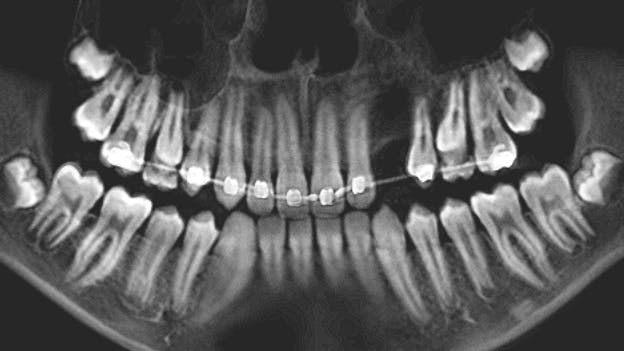

Dental history included a small amount of caries with an anterior crossbite (end to end), as well as a habit of biting his lower lip with his teeth. The patient had been seen three times in the last three years; the parents did not bring the child to the dental office for regular checkups. At a visit six to seven months ago, the patient had a sore lower lip from biting it all day. There were no soft-tissue findings at the time.

At the recare visit, caries was not present and there was no change in the patient's health history.